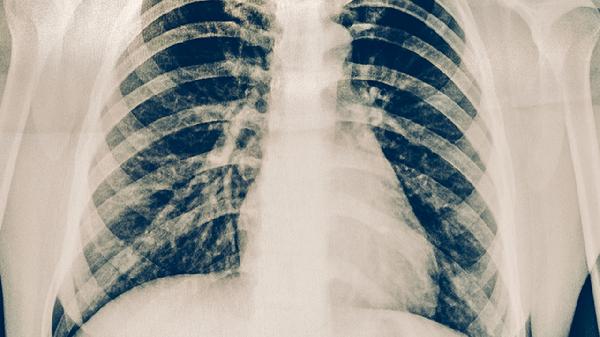

肋骨骨折后,骨折端需要经历炎症期、修复期和重塑期三个阶段才能完全愈合。在炎症期,骨折部位会出现肿胀、疼痛等症状,通常持续1-2周。修复期是骨折愈合的关键阶段,骨折端开始形成骨痂,一般需要3-6周。重塑期是骨折愈合的最后阶段,骨痂逐渐被成熟的骨组织替代,通常需要6-8周。对于单纯性肋骨骨折,没有合并血气胸等严重并发症的患者,一般4-6周可以恢复正常活动。如果骨折端移位明显或合并其他损伤,恢复时间可能延长至6-8周。在恢复期间,患者应避免剧烈运动和重体力劳动,防止骨折端移位或再次受伤。疼痛明显时可以遵医嘱使用止痛药物,如布洛芬缓释胶囊、对乙酰氨基酚片等。同时要注意保持呼吸道通畅,避免咳嗽、打喷嚏等动作加重疼痛。

肋骨骨折患者在恢复期间应注意休息,避免剧烈运动和重体力劳动。可以适当进行深呼吸练习,防止肺部感染。饮食上应保证充足的蛋白质和钙质摄入,如牛奶、鸡蛋、鱼肉等,有助于骨折愈合。睡眠时建议采取半卧位,减轻骨折部位的压力。如果出现呼吸困难、胸痛加重等症状,应及时就医复查。定期复查X线片可以了解骨折愈合情况,医生会根据恢复情况调整治疗方案。